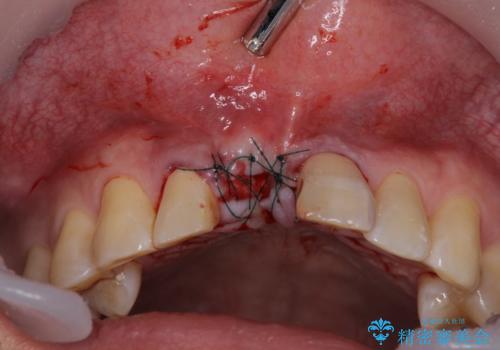

咬合力が非常に強いため、インプラントにも過度な力の負担が発生する恐れがあります。

長期間安定して使用いただくために、睡眠時のマウスピースの装着による咬合力の分散が必要となります。